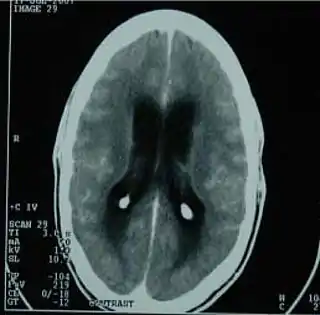

![]() TAC del cerebro mostrando una meningitis tuberculosa. | ||

La meningitis tuberculosa es una forma grave de meningitis bacteriana causada por Mycobacterium tuberculosis. Se diferencia de otros tipos de meningitis infecciosa por el curso clínico de evolución más lenta. Los síntomas iniciales son similares a los de otros tipo de meningitis, fundamentalmente fiebre, cefalea, rigidez de nuca y convulsiones. Es una afección grave que puede dejar como secuela déficits neurológicos permanentes.[1]